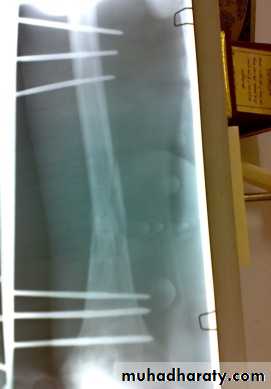

In old internal fixation is often preferable and the patient can get out of bed sooner (dynamic condylar screw and plate) .

dynamic condylar screw and plate

Supracondylar fracture with its fixation by L – plate and screws